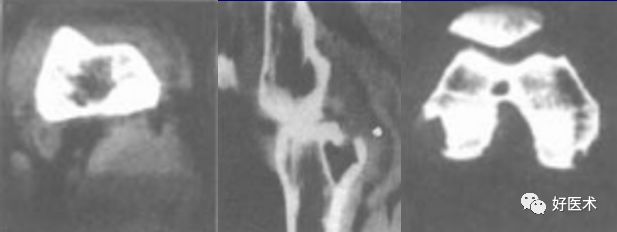

CT表现

CT可清楚显示病变的范围,对于显示关节软组织肿块、关节囊肥厚、关节积液及微小的骨侵蚀方面较 X线平片敏感

关节周围可见卵圆形软组织肿块,股骨髁及胫骨见骨质破坏